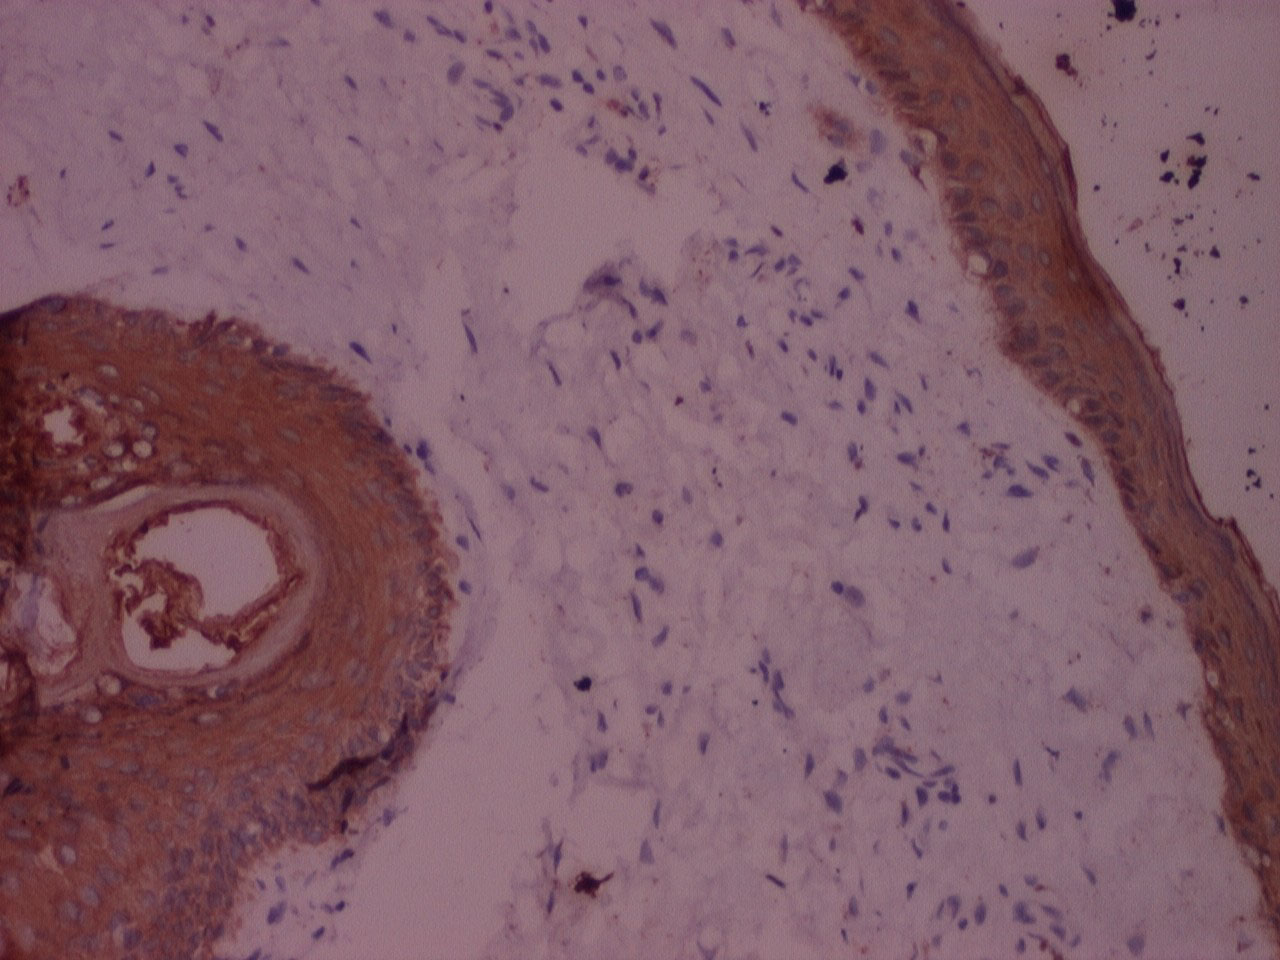

Figure 5: IHC stained photomicrograph of section showing cytokeratin positivity, processed with n-Heptane, 10x. View Figure 5

The majority of the samples processed with n-Heptane showed weak to moderate IHC staining for cytokeratin and vimentin (Figure 5, Figure 6, Figure 7, Figure 8 and Figure 9) with none of the sections devoid of staining.